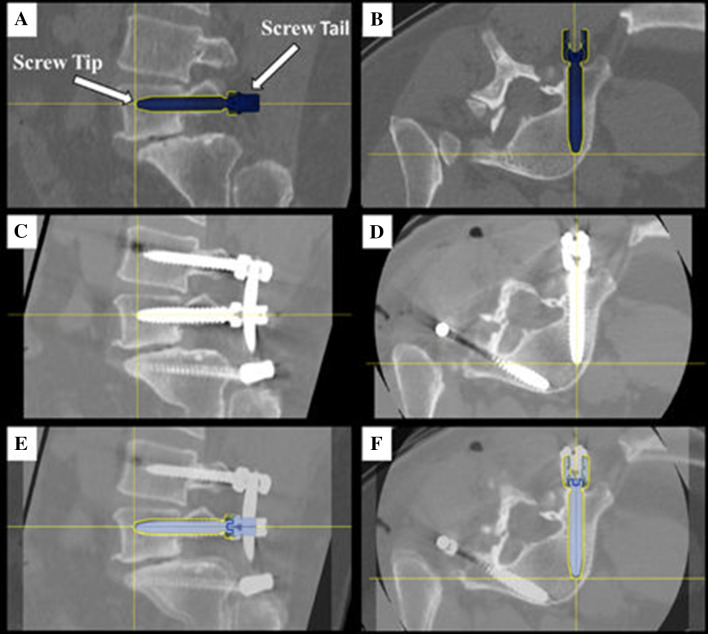

A CT-based Gertzbein and Robbins System (GRS) was used to classify pedicle screw accuracy, in which screws were graded as A (screw is completely within the pedicle), B (pedicle cortical breach < 2 mm), C (pedicle cortical breach < 4 mm), D (pedicle cortical breach < 6 mm), and E (pedicle cortical breach > 6 mm) [4]. The evaluator was blinded to the study groups. Screws with an A or B grade were deemed as accurate while screws with a C, D, or E grade were considered inaccurate, as previously demonstrated [4–7]. The number of accurate screws divided by the number of total screws placed with robotic navigation resulted in an accuracy percentage for the first 101 cases. Additionally, quantitative three-dimensional screw tip, screw tail, and screw angulation offsets were determined using CT scans and image overlay analysis to compare preoperative planned trajectories to actual postoperative screw placement (Fig. 1). Pedicle screw malposition, reposition, and return to operating room (OR) rates were collected.

Fig. 1.

Lumbosacral pedicle screw planning and placement with a minimally invasive navigated robot-assisted pedicle screw positioning system

Screw tip, tail, and angle offset assessment. Right L5 screw planning in (a) sagittal and (b) axial planes. Image overlay analysis with preoperative planned trajectory and postoperative screw placement in (c) sagittal and (d) axial planes. Postoperative CT of L5 screw placement without a medial or lateral breach in (e) sagittal and (f) axial planes. The crosshairs indicate screw tip

The average offset from preoperative plan to actual final placement of left-side (resident) screws was 1.74 ± 1.31 mm from tip, 1.75 ± 1.24 mm from tail, and 1.98 ± 1.43° of angulation. The average offset from preoperative plan to actual final placement of right-side (attending) screws was 1.75 ± 1.39 mm from tip, 1.82 ± 1.14 mm from tail, and 2.11 ± 1.75° of angulation. Using an independent samples t test it was found that there were no significant differences between the left and right sides in tip, tail, or angulation offset (p > 0.05) (Table 3).